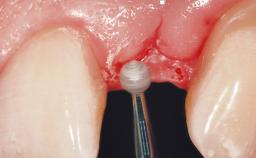

The video demonstrates implant placement using a surgical stent according to the principle of prosthodontically driven implant placement. The deficient ridge is augmented with locally harvested autologous bone chips, a superficial layer of xenogenic DBBM particles and a resorbable collagen membrane. The surgery is completed with a precise, tension-free primary wound closure.

The case concludes with the presentation of the final prosthesis and the esthetic outcome, demonstrating stable soft tissue conditions and stable bone crest levels at the 3-year follow-up.